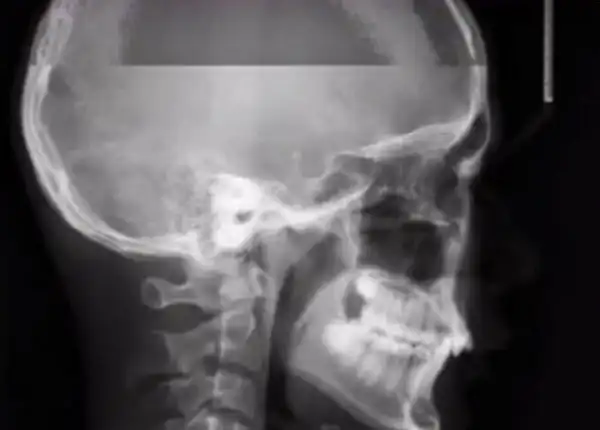

Вот так, как на этом фото, выглядит обычный рентген. А вы когда-то задумывались над тем, как будет выглядеть рентген, если пациент случайно чихнет во время создания снимка? Хотите взглянуть на то, что из этого вышло? Тогда смотрим.

Да, это результат рентгена, во время которого пациент чихнул.